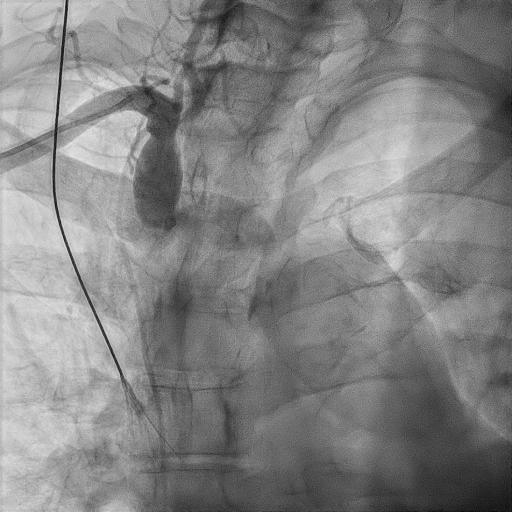

ECG showed sinus rhythm. 24hours ECG ( Holter ) showed ectopics < 1% , pause < 2secs [not significant].Echo showed EF 45-50% with hypokinesia (as shown above) – no thrombus or severe aortic stenosis. Creatinine was ~130umol/L ( not markedly raised).Ad hoc Coronary Angiography was performed:LM <30% stenosesLAD Prox 70-80%LCx ISR (Prox-Mid) 80-90%RCA ISR (Pros) 80% , DominantPCI to LCx ISR – DEB 2.75/20mm , PCI to LAD (ostium-mid) – DES 2.75/33mm + 3.5/13mm

Relevant Catheterization Findings

Now for staged PCI to RCA. Attempted engagement with a JR 3.5 6Fr via RRA.Challenges anticipated:1 subclavian tortuosity, noted from past angiography – needing gentle manipulation, avoid femoral access2 poor engagement due to ostium disease3 wiring from outside ( ¡®air-mail¡¯)Lesions are calcifed, diffuse, proximal(ostium RCA) and distal to stented segment - stent not covering ostium.Plan is to IVUS, prepare new lesions, prepare ISR segments then either hybrid DES/DEB or new DES all the way.

Diagnostic RCA.mp4